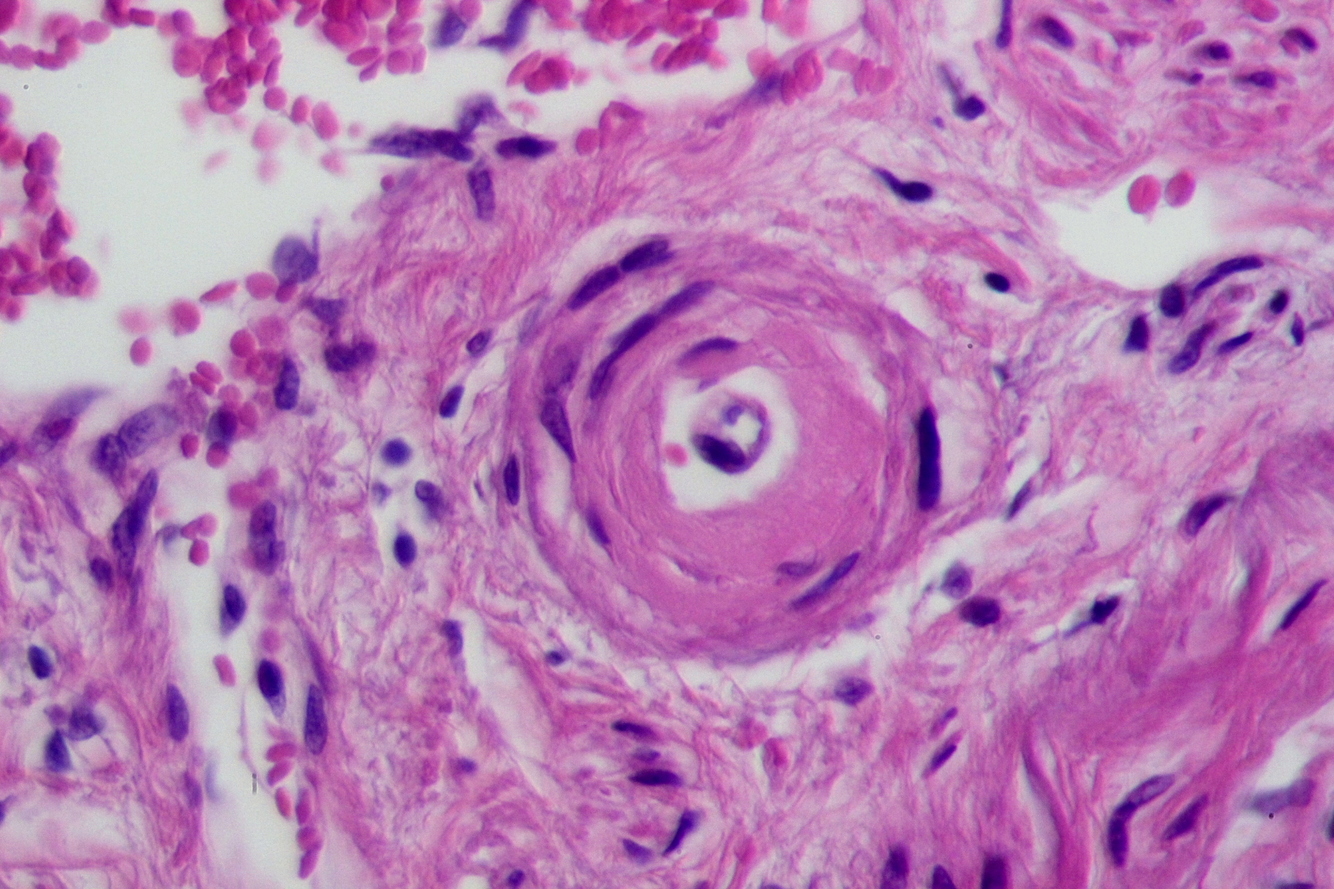

2. Hyperplastic arteriolosclerosis: thickening of cesel wall by hyperplasia of smooth muscle. Consequence of MALIGNANT HTN. May lead to fibrinoid necrosis of vessel wall with hemmorhage.